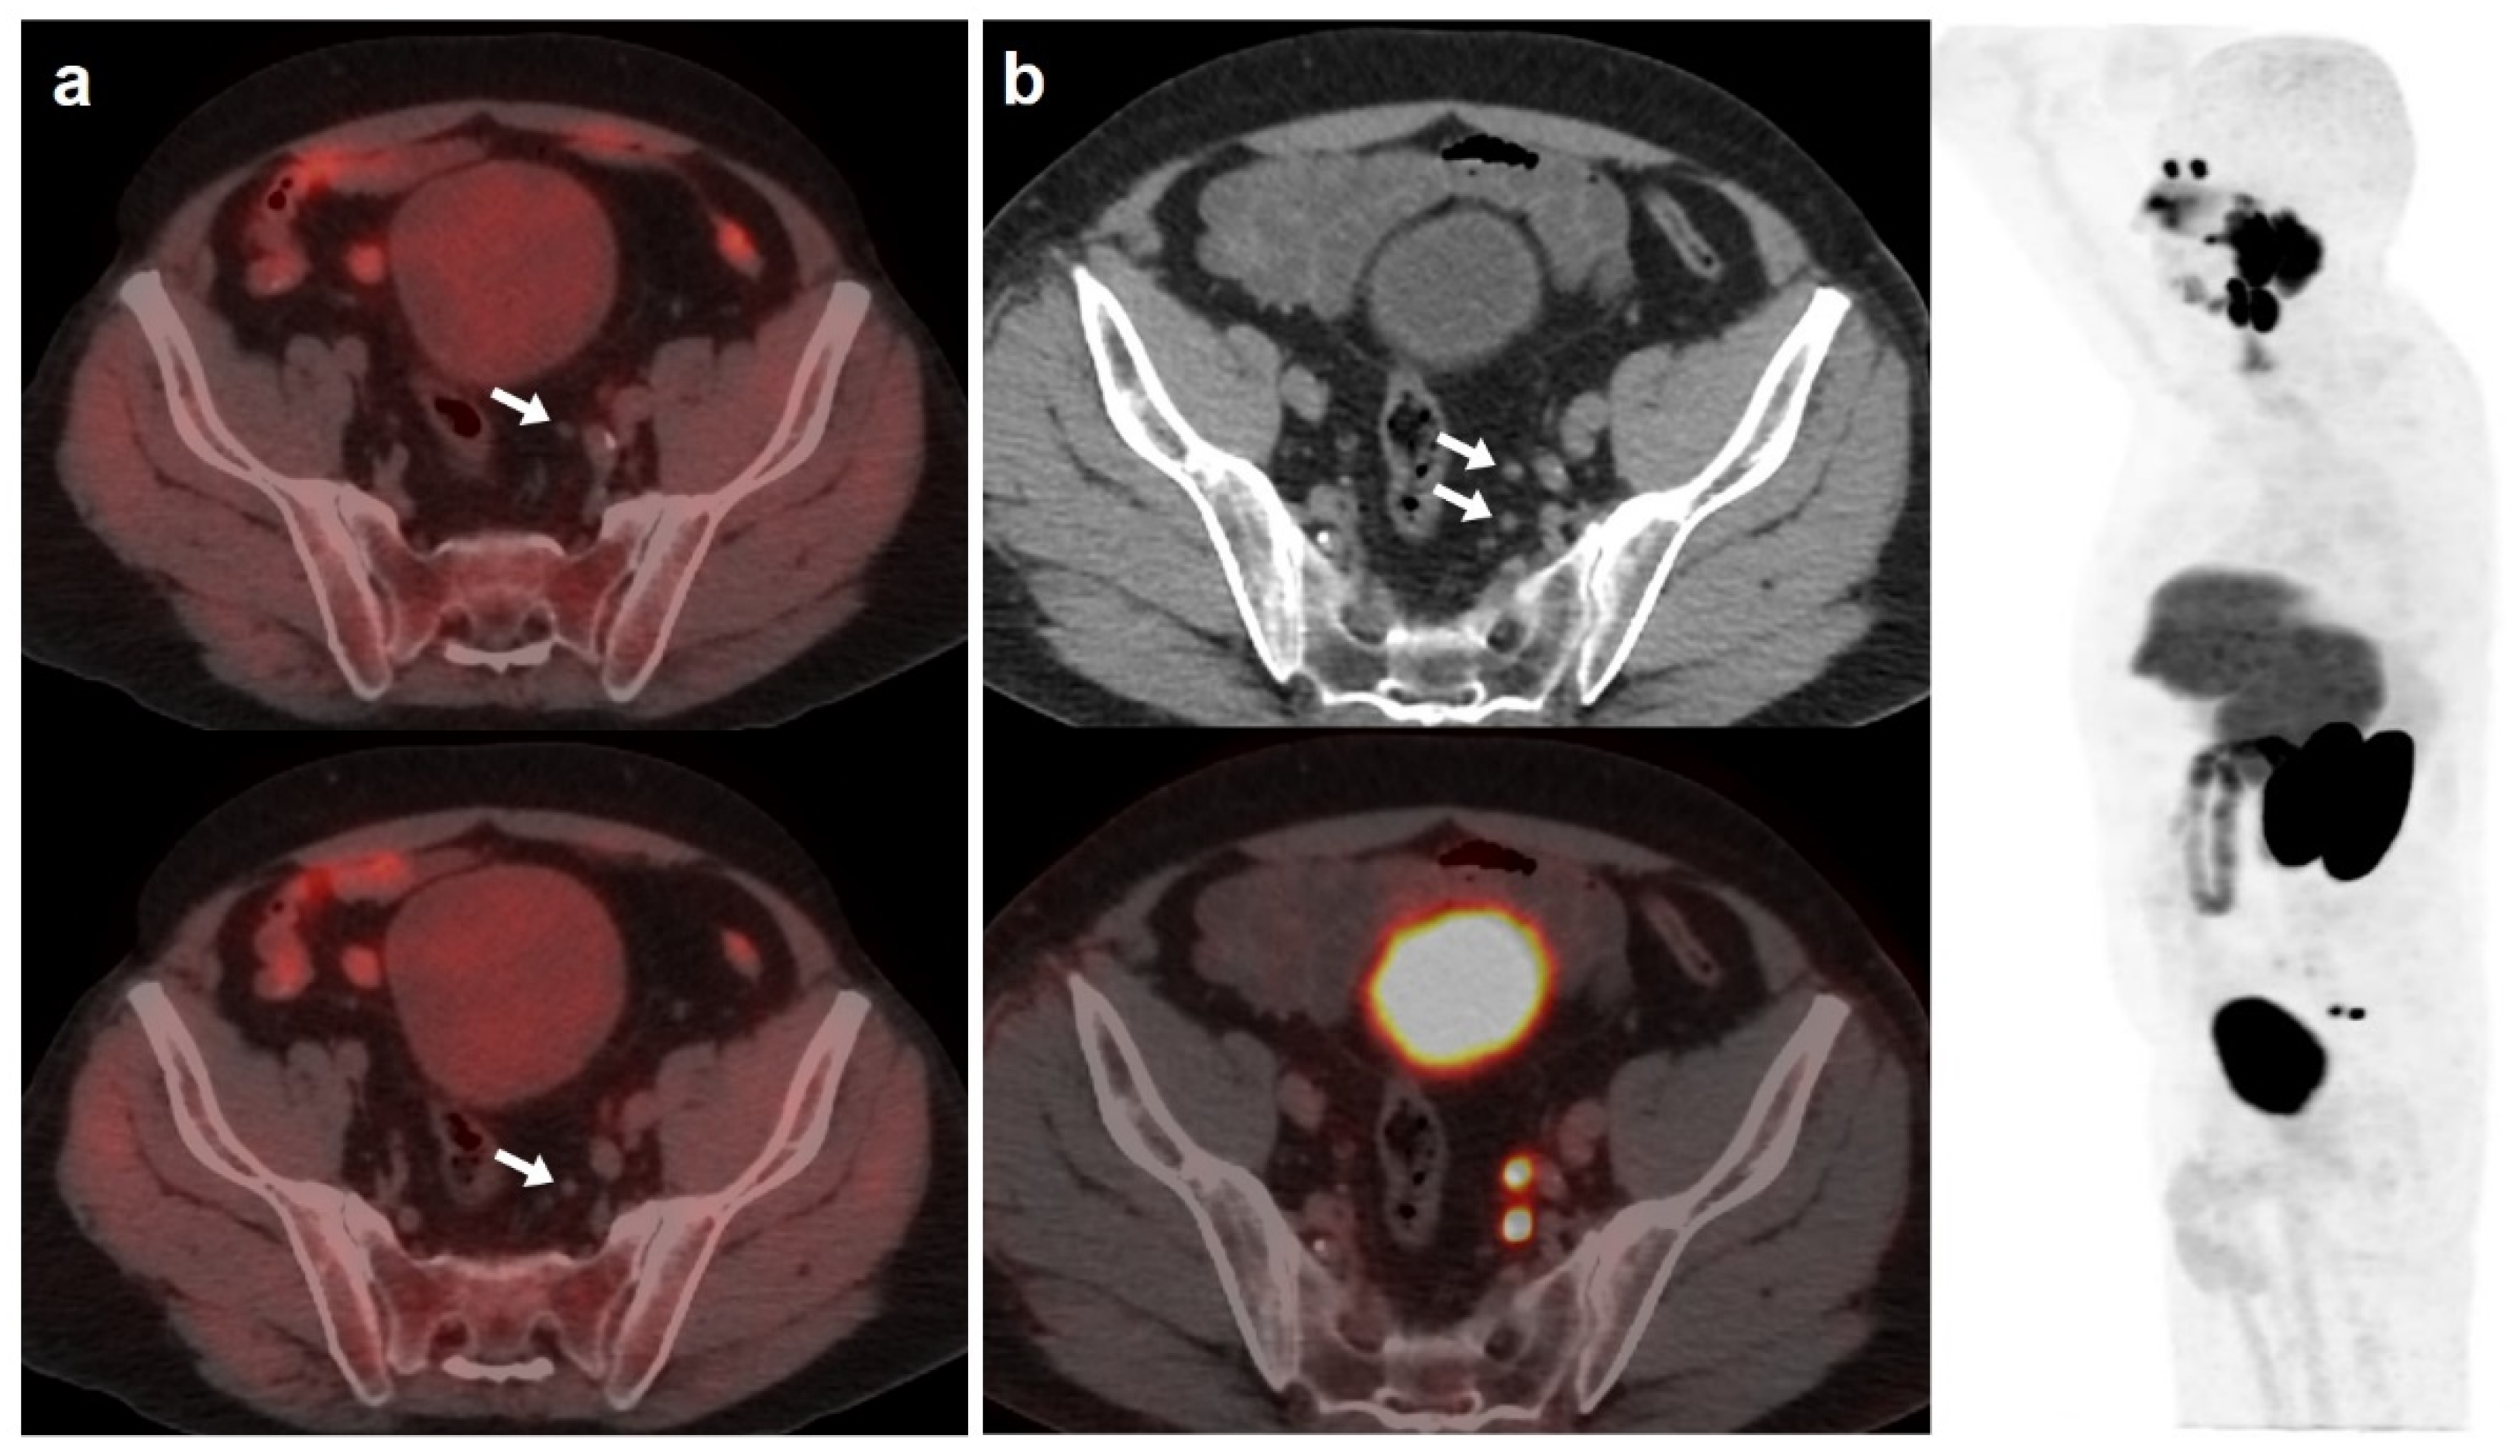

Figure 6.

56-year-old patient. PCa (Gleason 6) treated with braquitherapy. BCR (PSA: 5.4 ng/mL, PSAdt 6.17 months, PSAvel 0.55 ng/mL/month). [18F]F-choline (a) showed prostate gland uptake and right external iliac lymph nodes metastasis (white arrow). One month later, the patient was also scanned with [18F]DCFPyL (b) revealing only prostate gland pathological tracer uptake (white and black arrow). Prostate biopsy was negative (false positive). Follow-up was decided and PSA level keeps oscillating (4–5 ng/mL) with an additional negative [18F]DCFPyL-PET/CT one year later.